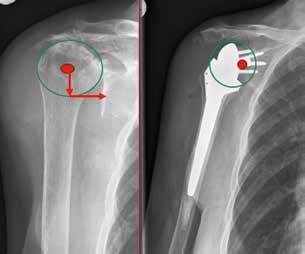

Weltweit werden die meisten Schulterprothesen von Operateuren implantiert, die weniger als zehn Implantationen pro Jahr durchführen 1. Das bringt die Gefahr mit sich, dass sich die Zahl der Komplikationen erhöht. Die inverse Schulterprothetik führt durchaus zu einer guten Rekonstruktion der Funktion bei Patienten mit Rotatorenmanschettendefekten 2. Durch die Umkehrung von Konvexität am Glenoid und Konkavität am Humerus wird das Drehzentrum distalisiert und medialisiert, was zu einer Reduktion des Drehmoments und zu einem zusätzlichen Recruitment von Deltafasern führt (Abb. 1a u. b) 3.

Gleichzeitig entstehen jedoch Komplikationen wie Instabilitäten mit Luxation (Abb. 2), akromiale Frakturen sowie Lockerungen glenoidaler und humeraler Komponenten, die in dieser Art bei den bisherigen Prothesen nicht bekannt waren. Villacis et al. (2016) 4 untersuchten die Komplikationen nach Schultervollprothesen im Vergleich mit inversen Prothesen bei 10.844 Prothesen. Die Komplikationsrate bezüglich Infektion und Dislokation war unterschiedlich zu Ungunsten der inversen Prothesen.